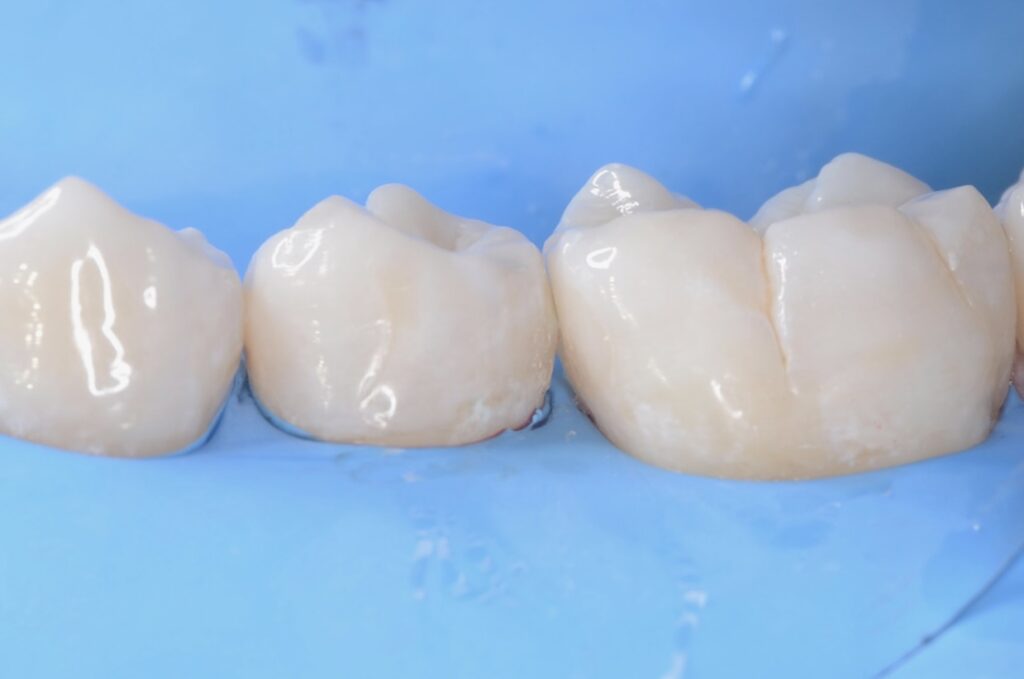

30代 虫歯治療 VPT(歯髄温存療法)ダイレクトボンディング #66

02虫歯治療(ダイレクトボンディング)

ダイレクトボンディングは、歯の欠損や小さな虫歯を即座に修復する方法です。歯と同色の材料を直接歯に盛り付け、自然な見た目と機能を取り戻します。

1本の歯は、一生の間にわずか5回しか治療に耐えられないと言われています。すなわち5回以上治療すれば抜歯に近づくのです。

だからこそ、虫歯にしない。

万が一虫歯になってしまったら、できるだけ早めに治療する。

最小限に削って、精密に治す。隙間があれば、そこから虫歯になるから。

決して裸眼で治療はできません。それが、私たちが拡大視野で丁寧な治療にこだわる理由です。